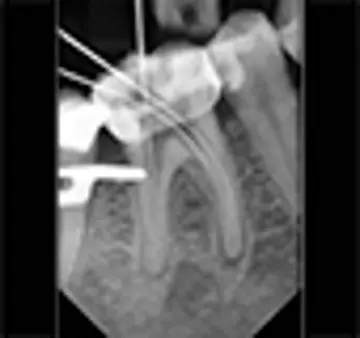

دندانپزشکی - صفحه 5